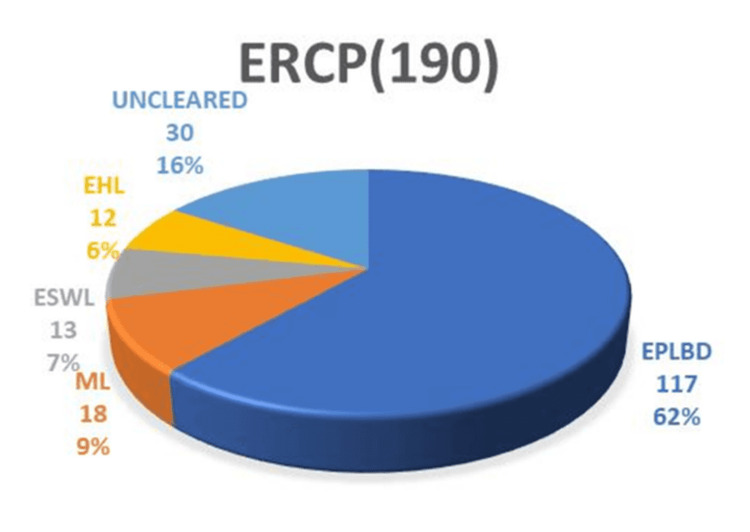

Results: The study achieved an overall CBDS clearance rate of 650/682 (95.3%), with a clearance rate of 160/190 (84.2%) for difficult stones. For difficult stones, endoscopic papillary large balloon dilation (EPLBD) alone was successful in 117/190 (61.5%) cases. Additional interventions, including mechanical lithotripsy (ML) in 18/190 (9.4%) cases, extracorporeal shock wave lithotripsy (ESWL) in 13/190 (6.8%) cases, and electrohydraulic lithotripsy (EHL) in 12/190 (6.3%) cases, were required. The overall success rates for these interventions were as follows: EPLBD 117/175 (66.8%), ML 18/30 (60%), ESWL 13/20 (65%), and EHL 12/13 (92.3%). Surgical intervention was required in 30/190 (15.7%) cases. Complications occurred in 82 (12%) of overall cases and 13 (6.8%) of difficult stone cases.

ERCP was highly effective in clearing the common bile duct (CBD), with an overall success rate of 650/682 (95.3%). All non-difficult stones were successfully removed in a single session using endoscopic sphincterotomy, balloon, and/or basket sweeps, achieving a 490/490 (100%) success rate. Difficult stones, on the other hand, typically require 1.2 sessions for successful removal, necessitating additional interventions following papillotomy. The management of difficult stones in our study cohort involved various modalities. Figure 1 illustrates the distribution of modalities used to manage difficult stones.

Notably, the majority of difficult stones were cleared in the first session using EPLBD. The overall success rate of EPLBD with endoscopic sphincterotomy was 607/682 (89%). Only 29/190 (15.2%) of cases of EPLBD procedures were not attempted upfront due to narrow lower ends or strictures (Figure 2). In these cases, stenting was performed first, followed by other modalities in subsequent sessions.

The addition of ML to EPLBD and endoscopic sphincterotomy resulted in an overall success rate of 625/682 (91.6%). Figure 3 illustrates ML used in a patient. The addition of ESWL (Figure 4) resulted in an overall success rate of 638/682 (93.5%), and the addition of EHL resulted in an overall success rate of 650/682 (95.3%) for the endoscopic removal of stones (Figure 5).

However, in patients with difficult stones, the success rate of ERCP was slightly lower at 160/190 (84.21%). Table 3 shows the success rates of various modalities for difficult stones. Thirty of 190 patients (15.8%) were sent for surgery.